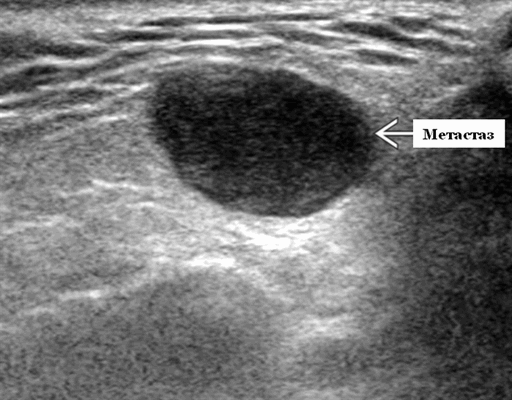

- Одиночные или множественные гипоэхогенные образования при известном распределении внутрипаротидных лимфоузлов.

- На ультразвуковом сканировании образование четко или плохо определено (экстранодальное распространение)

- На УЗИ определяется аномальная внутренняя архитектура ± эхогенные ворота, эхогенность однородная или неоднородная с внутренними кистозными участками в некротических узлах

Серошкальное УЗИ. Одиночные или множественные гипоэхогенные образования в известном распределении внутрипаротидных лимфоузлов. Хорошо выраженный или слабо окаймленный (экстранодальное распространение). Экстранодальное распространение. Обратите внимание на местную инвазию интрапаротидной наружной сонной артерии (ВСА), ретромандибулярной вены или экстрапаротидных мягких тканей. Аномальная внутренняя архитектура ± эхогенные ворота. Однородный или неоднородный вид с внутренними кистозными участками в некротических узлах ± метастазы в шейные лимфатические узлы